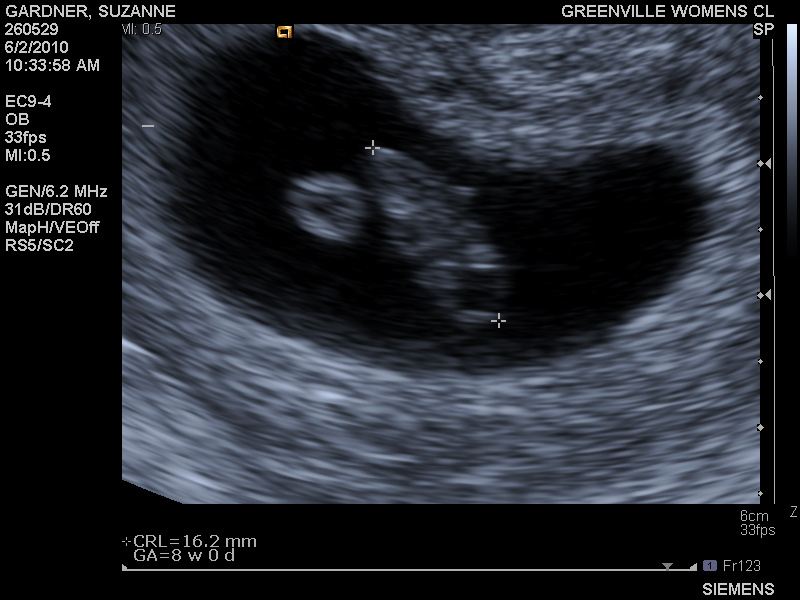

On May 4, 2010, the week of Mother's Day, we had another positive pregnancy test. I took a home test every day for a week, and finally had a blood test done a week later. My hCG was great, the progesterone level was low. Both were rechecked many times over the next several weeks. The hCG was going to levels I'd never experienced before. The progesterone level was staying low. I was started on an additional supplement, an intramuscular injection that I'd need once a week in addition to the Prometrium. The level still stayed low. The doctors were, once again, baffled. On 6/2 we had our first view of "Pookie" (nicknamed by our u/s tech) via u/s. She measured 8w0d and had the best sounding heartbeat we'd ever heard at a rapid rate of 175bpm. We were still a bit stunned we were pregnant, and even though things looked great overall, we were still very scared. We'd been through this before where everything is perfectly awesome ... until it isn't. Every week we had another ultrasound. Every week, Pookie had grown by leaps and bounds. On June 14, we not only heard that precious heartbeat, we saw her "dancing". The progesterone level continued to be low. We had one more option -- a supplement called Crinone that is used with IVF patients to help build up progesterone and uterine lining. The problem was, our insurance saw it as a fertility drug, so it cost $175 per week. We bit the bullet and went for it. Afterall, little Pookie was worth it. Meanwhile, our doctor called and wrote letters to the insurance company and the company that made the medication. After about 2 weeks, it was approved and now only cost a small copay.

7w3d